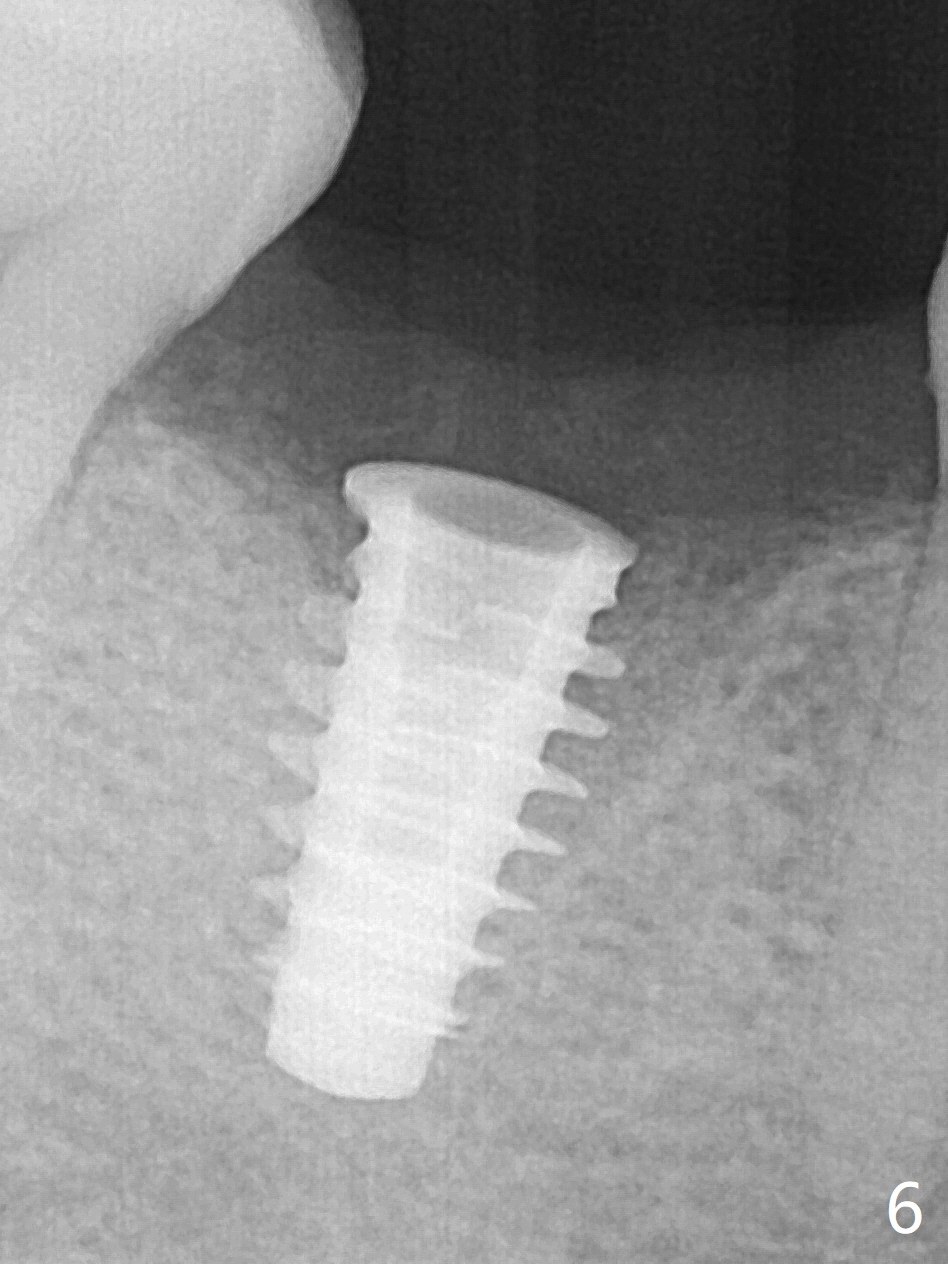

After removal of the residual roots at #30 (Fig.1), a thin septum (Fig.2 *) is removed with Rongeur (Fig.3). Following use of 4.8 mm Magic Drill, a 5x9 mm dummy implant is placed (Fig.4). To reduce socket gap (*), a 6 mm IBS implant is inserted with >50 Ncm (Fig.5). What is unexpected is heavy reduction in the height of a 6.5x4(3) mm abutment (A) because of the short crown height of the lower posterior teeth (Fig.1) and supraeruption of the tooth #3. The immediate provisional is unstable postop. The remade one dislodges soon, so does the abutment (Fig.6, 3 months postop). It appears that bone pattern in the distal socket changes.